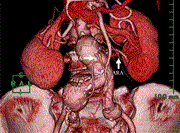

Successful treatment of a patient with a ‘flow-through’ type II endoleak associated with an aberrant renal artery after endovascular aneurysm repair

Masaya Sano and others

Journal of Surgical Case Reports, Volume 2023, Issue 3, March 2023, rjad087, https://doi.org/10.1093/jscr/rjad087